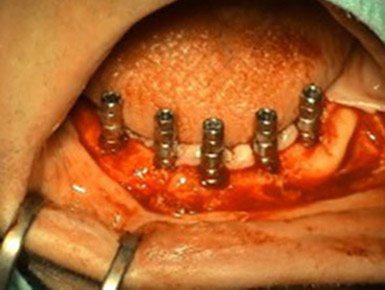

Prosthetic treatment in a toothless jawbone carried - 5 implants

1. PHASE - implant placement